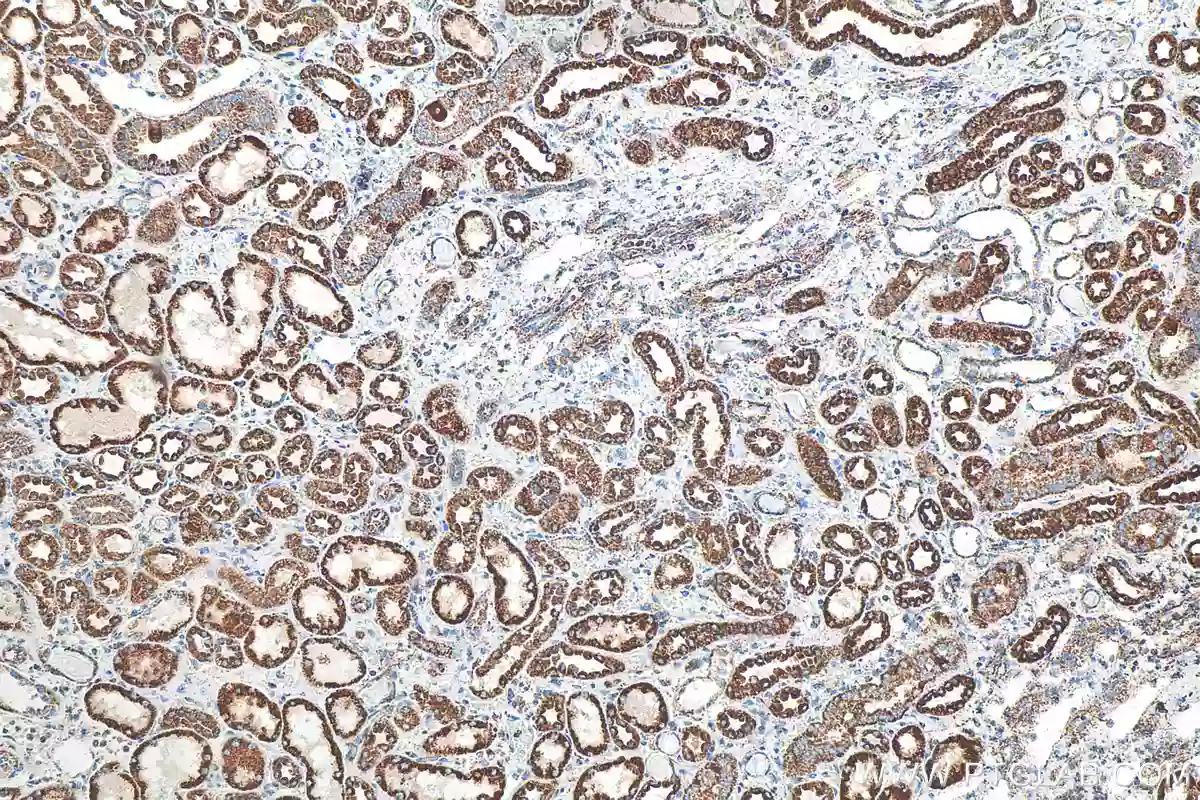

Nox4 Antibody 14347 1 Ap Proteintech